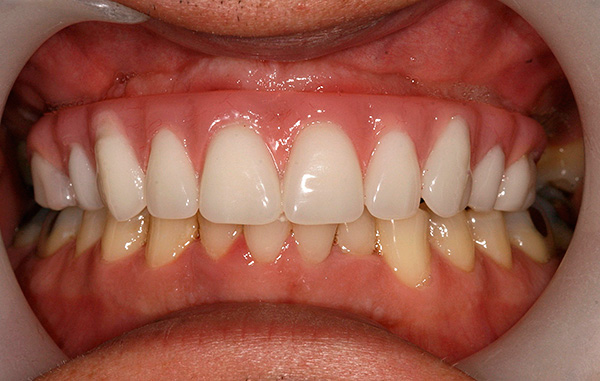

Os resultados das próteses usando a tecnologia All-on-4 parecem esteticamente agradáveis - exemplos são mostrados nas fotos a seguir.

Após o tratamento:

Depois:

A principal semelhança dos dois métodos é a possibilidade de carregamento imediato da prótese. E os objetivos da instalação instantânea das coroas são completamente idênticos - dar uma carga ao osso, restaurar a estética e a funcionalidade da dentição e estabilizar os implantes instalados. Nos dois casos, as dentaduras são criadas com gengivas artificiais, que escondem o contorno irregular da mucosa natural.

A foto abaixo mostra um exemplo de aparência da dentadura ao usar as duas tecnologias - All-on-4 e All-on-6: